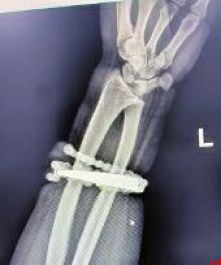

然而,就在两周前,龚女士的情况急转直下:手腕不仅疼痛加剧,还出现了明显的红肿,甚至有脓液渗出。她这才惊觉——手镯和串珠,已经有一部分“长”进了肉里,根本取不下来了!

“这是典型的首饰长期压迫、摩擦,加上细菌感染,引发的慢性炎症和肉芽组织增生。”医生介绍,此时,手镯和串珠已经成了一个不断刺激皮肤、污染伤口的“病灶”,如果不尽快手术取出,感染可能进一步扩散,手臂就保不住了,甚至会危及生命。

经过一个多小时的手术,医生们将手镯和串珠从厚厚的增生组织中完整剥离出来。目前,龚女士恢复良好,已顺利出院。